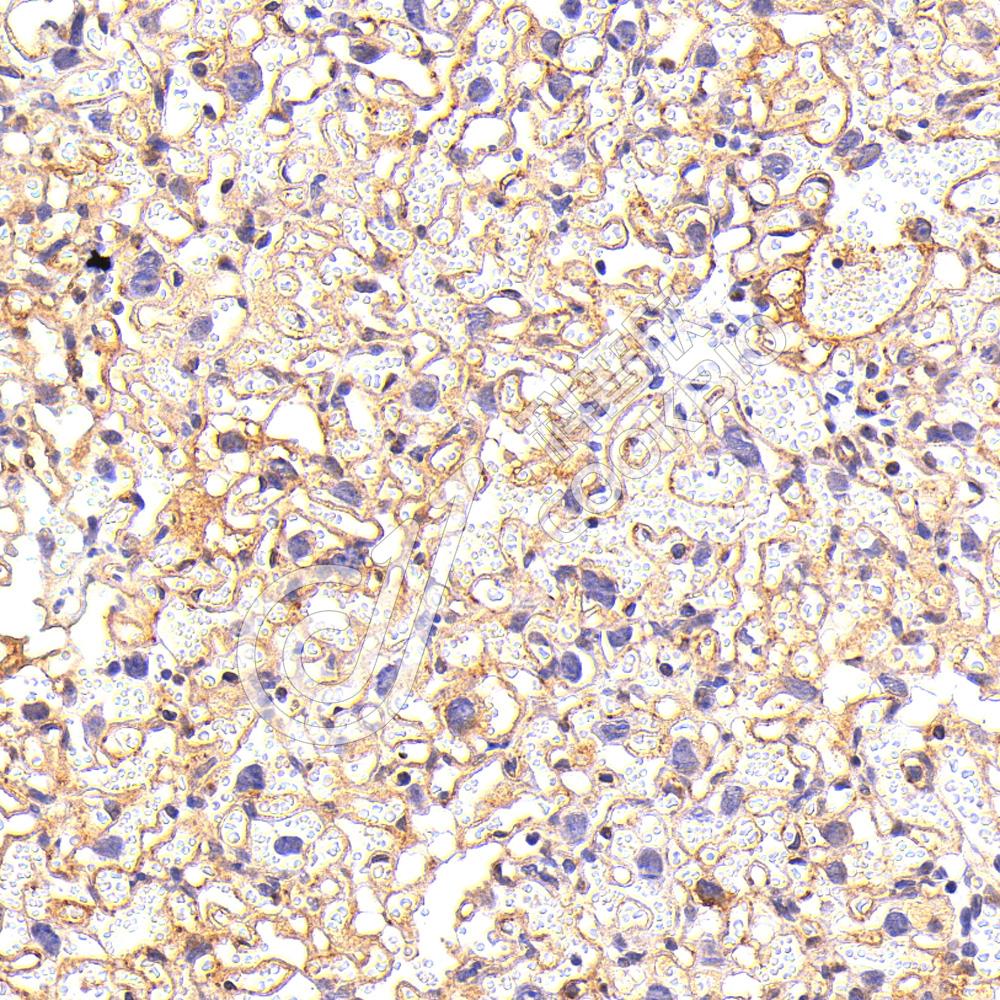

IHC检测CD73蛋白(货号 K1345522).

样品: 小鼠胎盘, 4%多聚甲醛 (货号KSG1101) 固定12-24小时.

抗原修复: 柠檬酸抗原修复液(干粉, pH 6.0) (KSG1201), 98℃, 20分钟.

—抗: 1: 500稀释, 4℃ 孵育过夜.

二抗: S-vision免疫组化多聚二抗(山羊抗兔),即用型 (货号KB3906), 室温孵育20分钟.